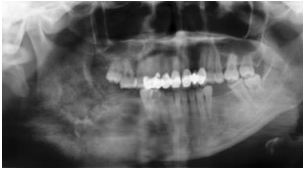

64.下列所附咬合片(occlusal film)中,對箭頭所指之放射線影像,最適切之描述為何?

(A)洋蔥皮狀影像(onion-skin appearance) (B)陽光線狀影像(sun-ray appearance) (C)羊毛棉花狀影像(cotton-wool appearance) (D)毛玻璃狀影像(ground-glass appearance)